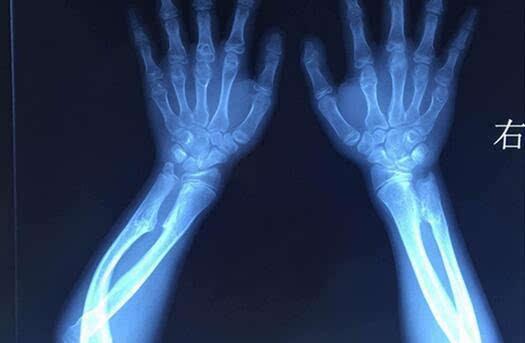

男性多发,肿瘤分布广泛且相对对称。在全身任何存在软骨的骨骼中几乎都有可能发生。由于肿瘤多发,所以很难依据外科手段全部切除。多表现为全身多发的骨性包块,常伴有骨骼短缩和畸形,如膝、踝、肘、腕关节的内外翻畸形。影像学上和单发的骨软骨瘤基本相同,只是肿瘤数量上的不同及存在骨骼畸形而已。